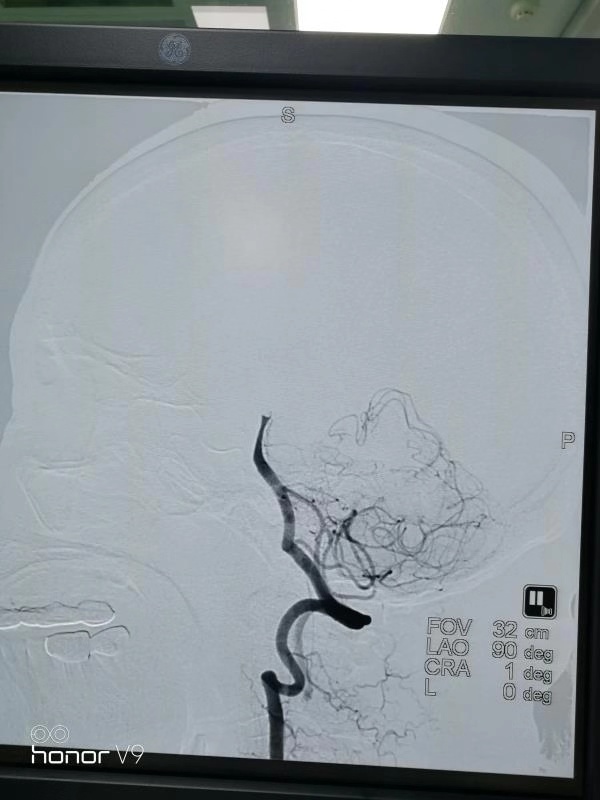

医生护士一顿忙碌,急诊造影看见阿婆基底动脉尖闭塞(黑色的血流线条突然中断)。